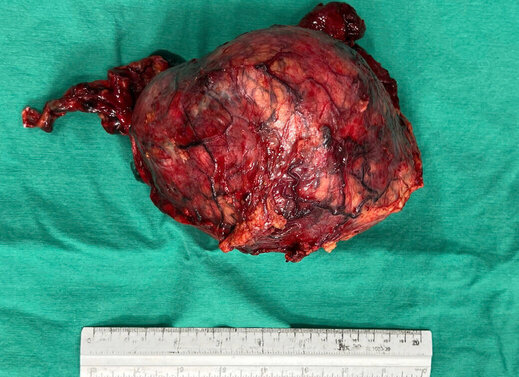

Theo BSCKII. Võ Quốc Hoàn - Phó Trưởng phòng Kế hoạch tổng hợp, bác sĩ Khoa Ngoại Tổng hợp, người trực tiếp thực hiện ca phẫu thuật cho biết: Ca phẫu thuật thuộc nhóm phẫu thuật tiết niệu – ung bướu có độ khó và nguy cơ cao do kích thước u rất lớn: chiếm trọn ổ thận, gây hẹp trường mổ, hạn chế thao tác bóc tách.

Bệnh nhân được chuẩn bị kỹ trước mổ, được truyền máu, đánh giá toàn diện chức năng tim, phổi, thận. Trong mổ, ê-kíp tiến hành cắt thận trái kèm khối u toàn bộ, đồng thời mở tĩnh mạch chủ dưới lấy huyết khối, bảo tồn tối đa cấu trúc mạch máu và chức năng thận phải.